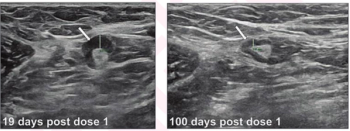

In a large study of nearly 100,000 women, researchers found that the combination of digital breast tomosynthesis (DBT) and synthesized mammography had more than triple the detection rate for invasive breast cancer in extremely dense breasts in comparison to digital mammography alone.

In a retrospective review involving over 2.2 million women with three consecutive biennial mammography screenings and no history of breast cancer, researchers noted that for premenopausal women with fatty breasts at baseline, increasing breast density at subsequent screenings led to significantly elevated hazard ratios ranging from 1.45 to 1.93 for the risk of breast cancer.